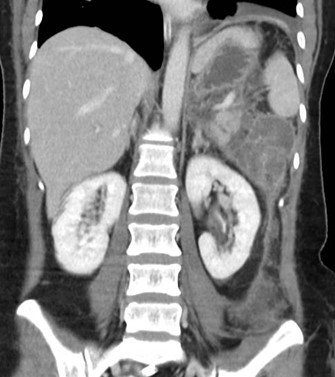

Mujer de 36 años que ingresa a Hospital Sanatorio Franchin el 11 de octubre de 2023 de forma programada para realización de duodeno pancreatectomía cefálica por tumor de cabeza de páncreas en estudio. Refiere hallazgo de lesión en forma incidental durante estudio de control hace dos meses por presentar antecedentes familiares (neoplasia endocrina múltiple). Se interna para manejo quirúrgico. Estudios de tomografía revelan formación nodular localizada en cabeza y cuerpo pancreático de paredes gruesas que mide 24 x 28 mm, que en resonancia se muestra hiperintensa en T2 y realce periférico luego de la administración de contraste endovenoso. Presenta restricción en la difusión con caída de la señal ADC, por lo que se vincula con una lesión de alta celularidad.

Tomografía de abdomen y pelvis con cte ev: del 13/10/2023.

Complicaciones posquirúrgicas

Tomografía de abdomen con cte ev: del 20/10/2023.

Tomografía de abdomen con cte ev: del 26/10/2023.